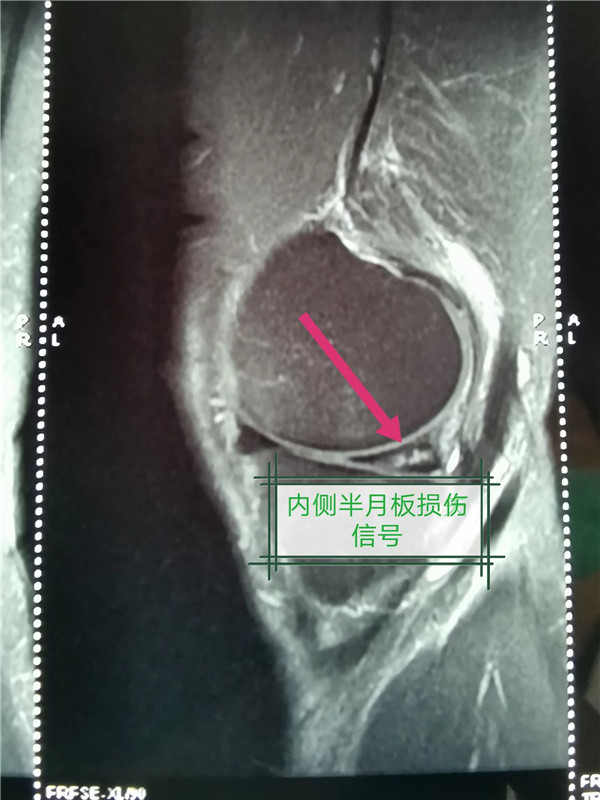

近日,骨一科为一位左膝关节反复疼痛的患者朱先生关节镜下行左膝内侧半月板后角撕裂成型术。据了解,朱先生膝关节一年来反复疼痛不适,多次就诊其他医院,并行多次针灸、敷草药等治疗,症状当时有好转,但很快又会出现疼痛,一个月前症状突然加重,影响行走活动,上下楼梯非常困难,再次行中医治疗,并口服消炎镇痛药,无任何效果。朱先生于6月21日就诊于市三院骨一科进行进一步治疗,刘华凯副主任医师完善相关检查,考虑半月板损伤可能性极大,行左膝关节MRI后提示:左膝内侧半月板后角撕裂。在与患者沟通后,刘华凯为该患者在关节镜下行左膝内侧半月板后角撕裂成型术,术后第二天便能下地行走,疼痛明显缓解,术后三天顺利出院,良好的治疗效果受到了患者和家属的一致好评。